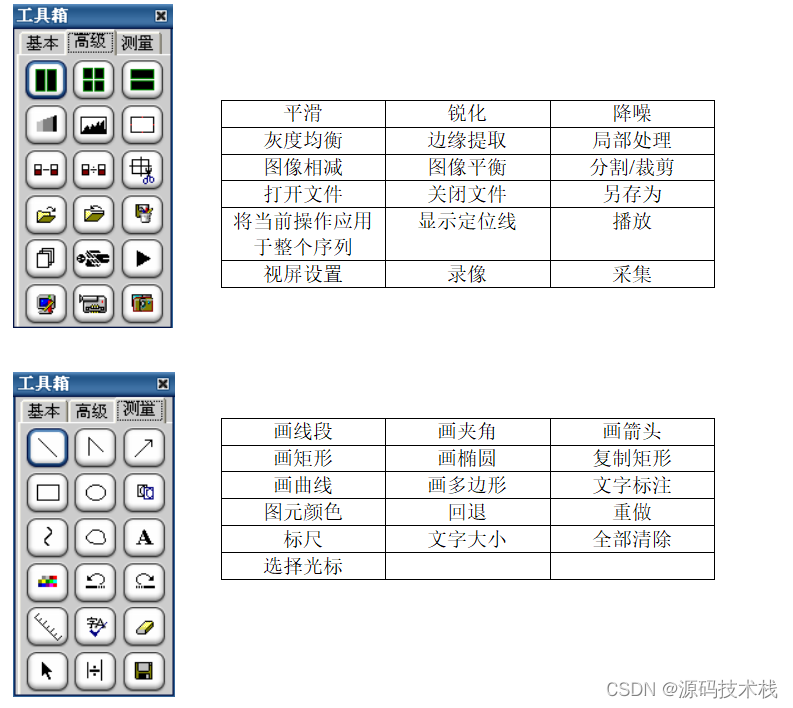

影像处理和测量功能

系统支持支持窗宽、窗位预设,连续调整窗口准位和直方图,图像均衡、图像平滑处理和边缘增强;

支持对比度调节、正负像旋转、影像黑白反转、影像水平和垂直翻转、灰阶转换和任意角度旋转等;

支持滤波、锐化、播放和彩色绘制等;

支持ROI值、长度、角度和面积等数据测量与计算;

支持数字减影、无级缩放和局部放大;

支持文字和图形标记;查询和保存DICOM头信息;

支持不同影像格式转存;

支持根据检查项目自动应用相应的预设窗宽、窗位。